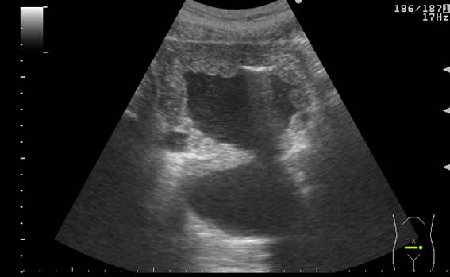

УЗИ мочевого пузыря у пожилого мужчины выявлены следующие изменения.

Signs of chronic urinary retention; evident thickening of the urinary bladder mucosa; large diverticulas. Residual volume evlaluation required; full prostatic assessment is recommended.

But really there are two ones on these pictures.

неравномерное утолщение стенок мочевого пузыря,признаки застоя в мочевом пузыре,расширенные дистальные отделы мочеточников,на первом снимке-дивертикул?слева,уввеличенная отечная простата

Все верно, за исключением того что простаты на картинках нет. Здорово, что Вы заметили расширение мочеточников. Есть также воздух в МП после цистоскопии.